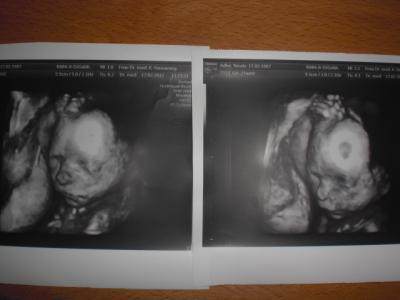

Hallo ihr lieben, nun melde ich mich endlich zurück! Ich war ja ein paar wochen nicht hier da ich umgezogen bin! Ich fass mich kurz versprochen! Also die Wohnung ist super schön das Kinderzimmer ist noch nicht eingerichtet aber zumindest stehen die babysachen vom großen schonmal da wo sie hingehören;) So und nun eine schöne Nachricht ich war vergangenen Freitag bei der feindiagnostik und was soll ich sagen.... Es wird ein Mädchen, sie ist gesund und munter und wog letzte woche noch ca. 400g! Nun heute hab ich die 23.Woche erreicht und es sind noch 17 lange die vor mir liegen! Bilder folgen sind echt schön geworden! Nun zu meiner Frage, wie sieht das bei euch aus, wieviel habt ihr bisher zugenommen? Also ich bin jetzt bei 6kg mehr Und ihr, bin echt neugierig was euer schnitt ist! Freu mich schon auf eure Antworten und hoffe es motiviert mich das es vielleicht nicht soviel ist wie ich glaube, ich komm mir ziemlich fett vor! Bauchbild ist von heute

ich hoffe ihr könnt es erkennen?

Hallo! Schöne Ultraschallbilder hast du! Habe gestern auch ganz tolle von meiner kleinen Maus bekommen! Bei mir fängt morgen die 26. Woche an. Ich habe jetzt 8 kg zugenommen. Meine FA meinte gestern, das wäre völlig normal. Meine Kugel ist wirklich schon riesig. Aber ich erwarte auch das dritte Kind und meine FA meinte, dass der Bauch von SS zu SS schneller groß wird... Zu Deinem Bauchbild: Ich finde das ist überhaupt nicht "fett" wie du selber schreibst.... 6 kg ist völlig in Ordnung. Mach dich nicht verrückt! LG Babynummerdrei